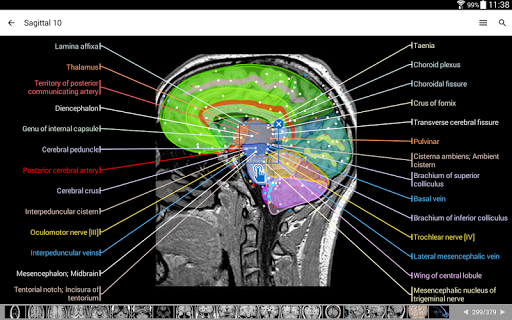

e-Anatomy tiene más de 26 000 imágenes que contienen series de imágenes en vistas axiales, coronales y sagitales, así como radiografías, angiografías, imágenes de disección, gráficos anatómicos e ilustraciones. Todas las imágenes médicas fueron etiquetadas cuidadosamente, más de 967 000 etiquetas disponibles en 12 idiomas, incluida la Terminologia Anatomica latina.

- Toque las etiquetas para mostrar las estructuras anatómicas

- Seleccione las etiquetas anatómicas por categoría